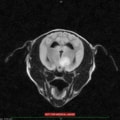

MRIの結果、頚部に脊髄空洞症を認め、頭部では水頭症および側脳室など脳内に数か所の腫瘤性病変を認めた。

頭蓋内伝播をしていることから悪性度の高い腫瘤である可能性が疑わしく、症例の頚部痛の原因と考えられる脊髄空洞症、および水頭症はこの頭蓋内腫瘤に起因する二次性発症と考えられる。

本症例の腫瘤は頭蓋内に数か所存在しており外科的切除や放射線療法は適応しにくいため、抗がん剤による化学療法の適応となった。

本症例は現在も抗がん剤(ロムスチン)による治療および脳圧降下剤などの投与であるが、症状も無く経過良好である。